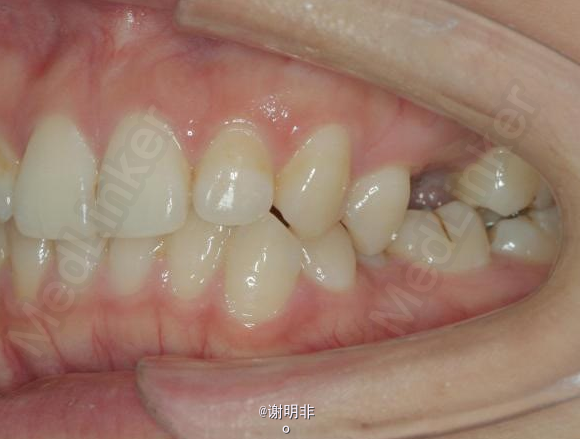

又一例不对称拔牙

牙弓狭窄,牙列拥挤

不对称拔牙